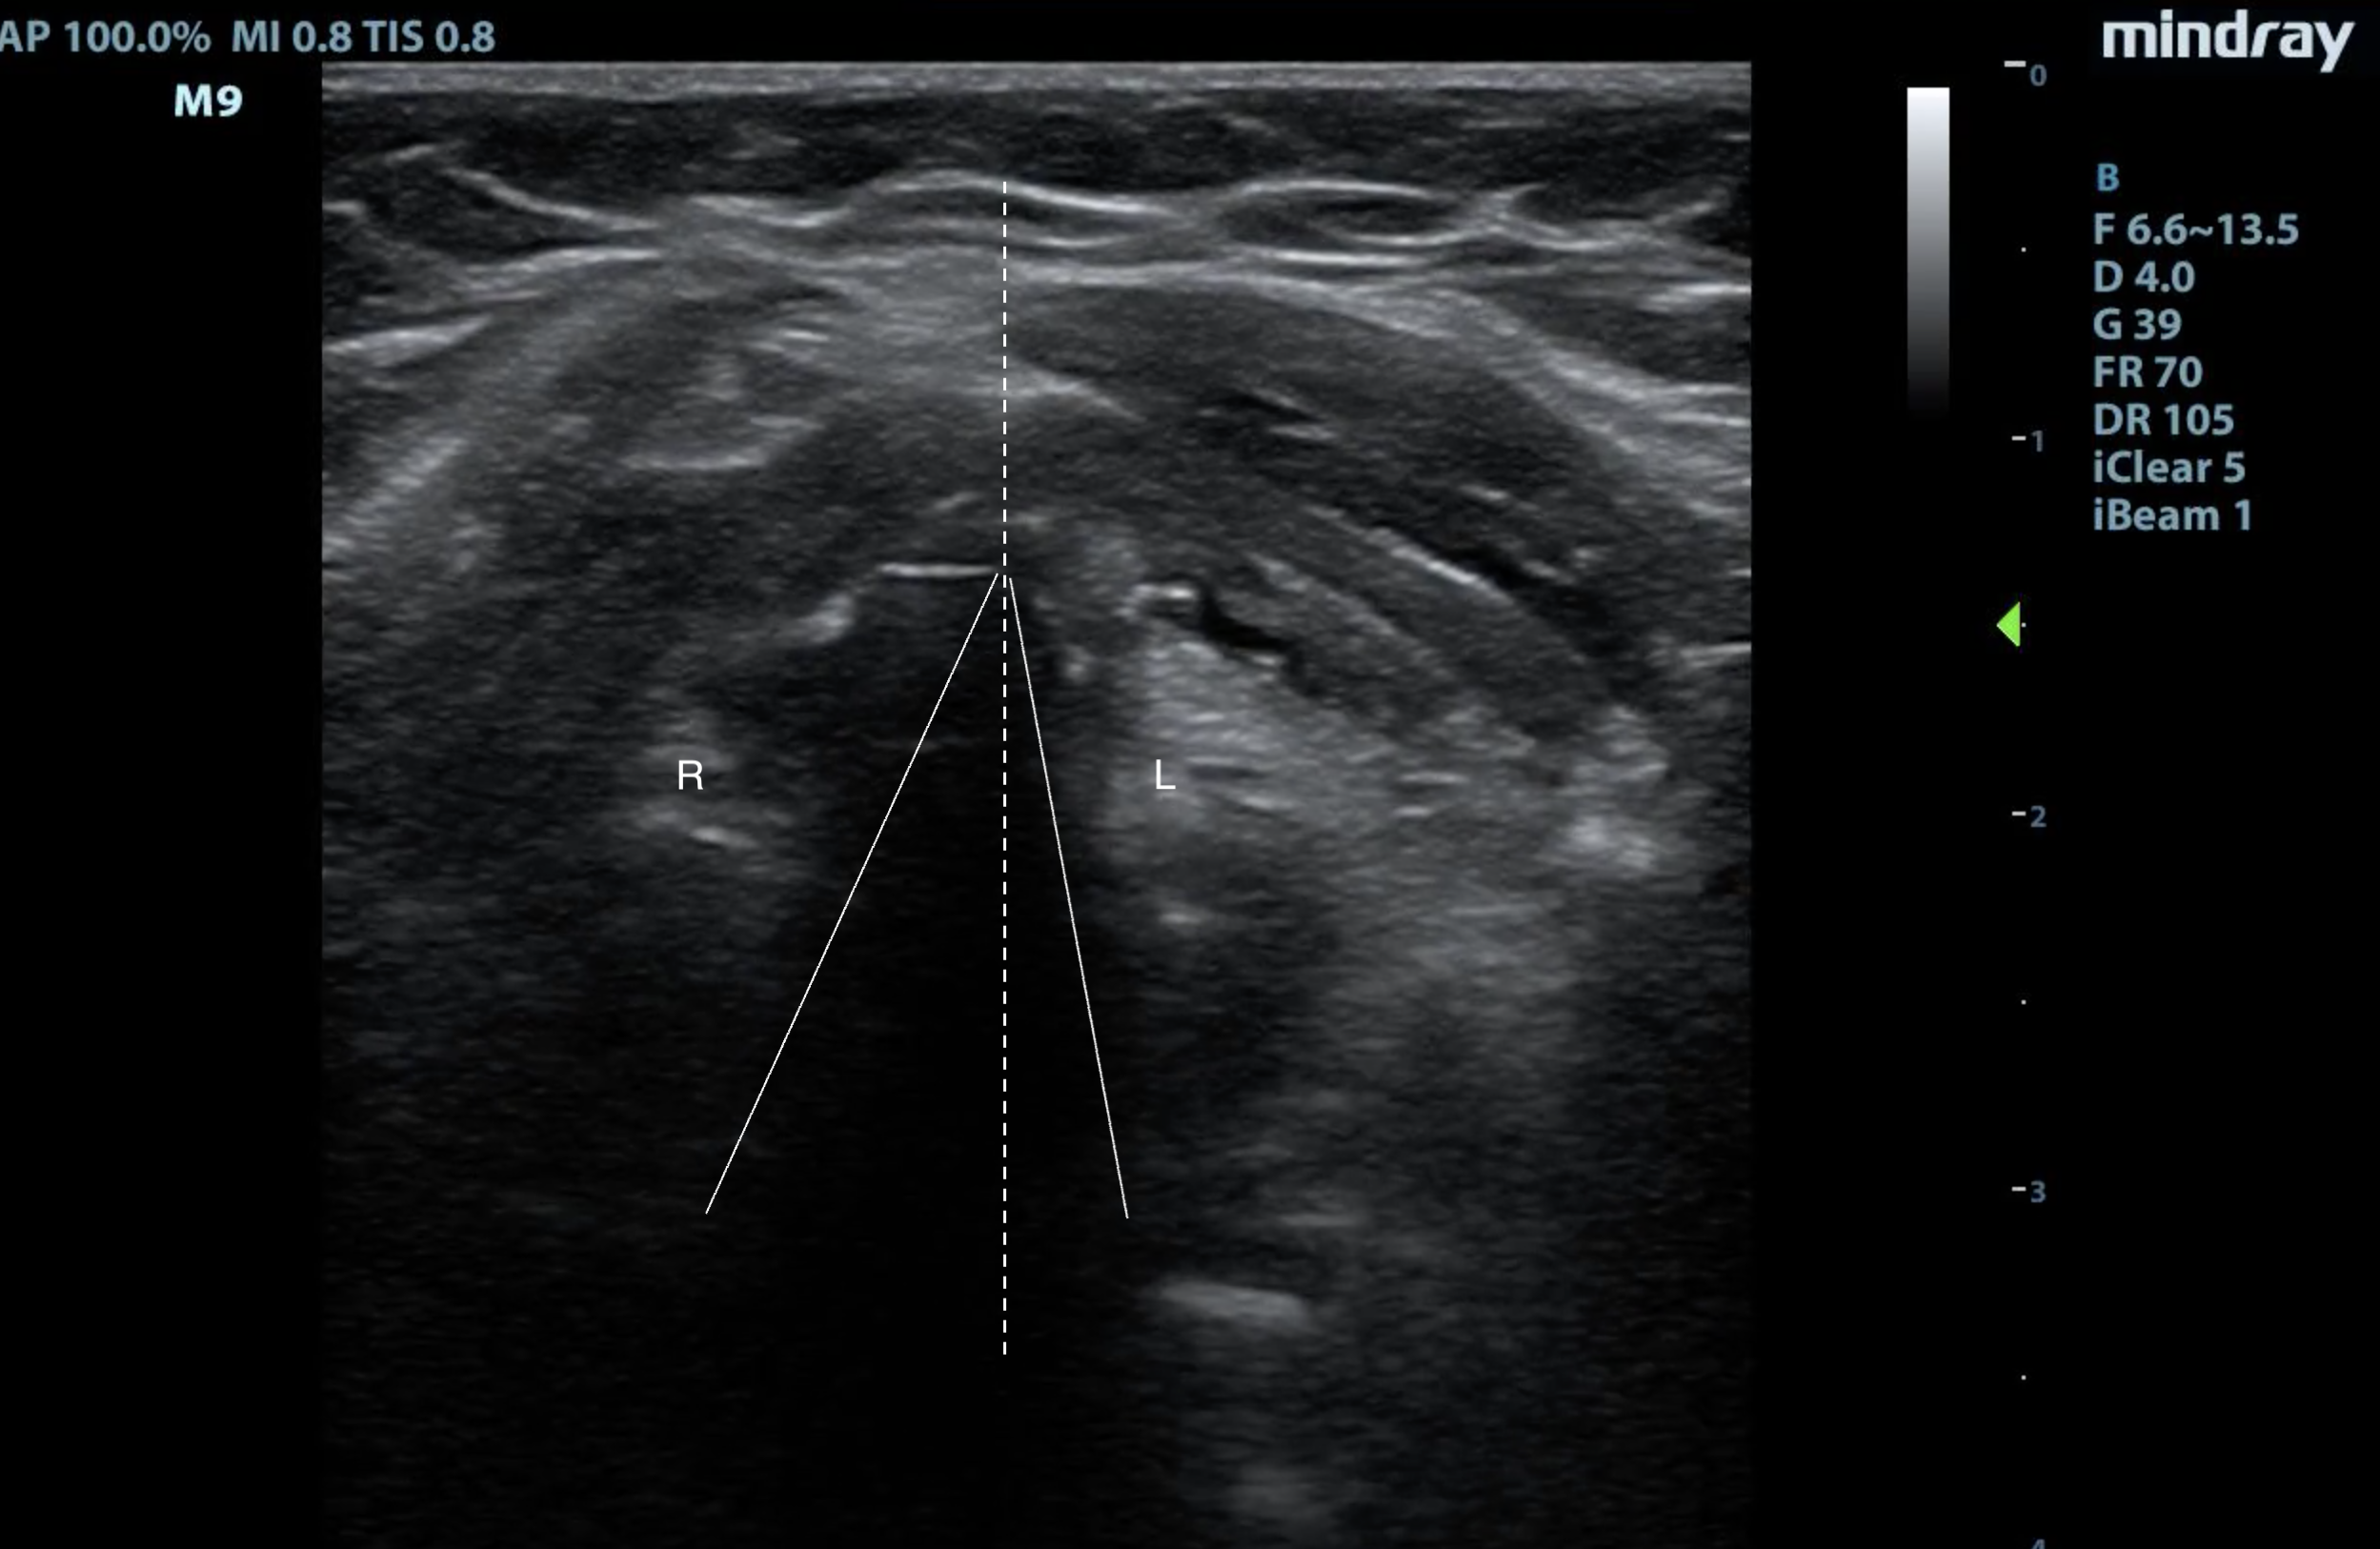

- While scanning, monitor for vocal cord movements, which normally is symmetrical. In patients with vocal cord dysfunction, asymmetrical movement or complete paralysis of vocal cords will be seen.

- Figure 9. This patient is trying to phonate, and the right vocal cord (R) is not coming to midline (dotted line), like the left vocal cord (L).